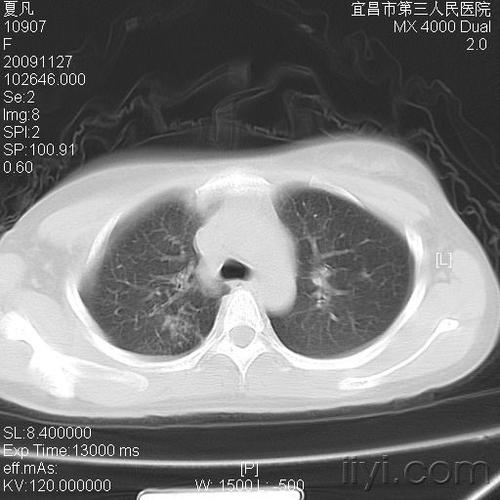

病毒性肺炎丨ct表现,诊断要点_小叶

病例 :男 岁患者,另一例小叶性肺炎.

② 小叶性肺炎